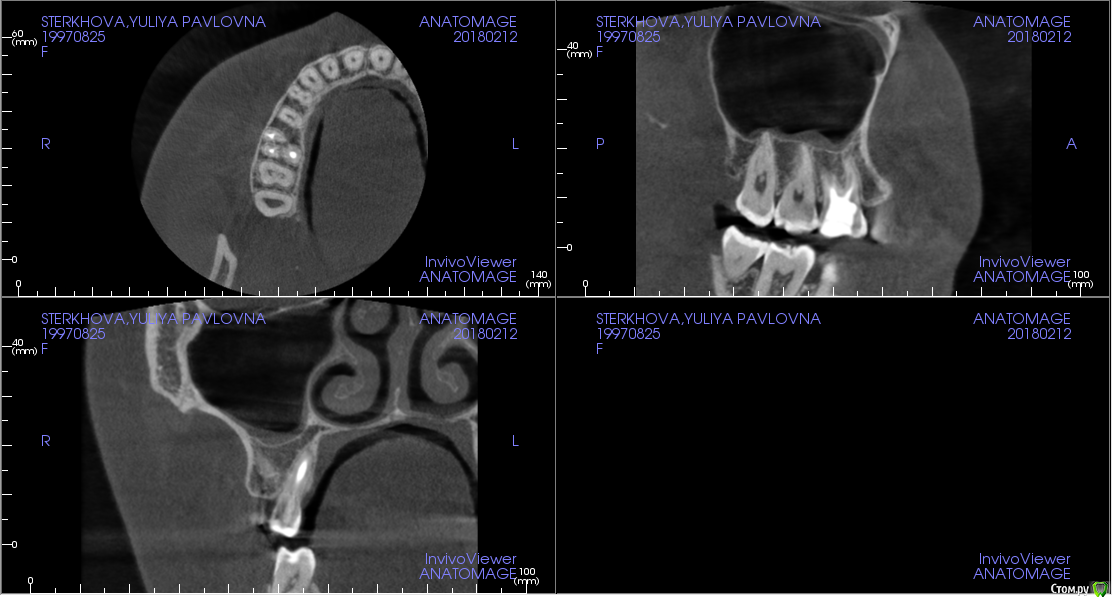

Стерхова Юлия Опубликовано 19 января, 2018 Автор Поделиться Опубликовано 19 января, 2018 спасибо за рекомендации. посетила уже третьего врача, тот тоже не нашел ничего, кроме воспаления десен (есть карман у зуба мудрости на этой же стороне сверху). предположил, что дело в дёснах, но меня этот ответ не удовлетворил. начинаю подозревать, что болят другие зубы, но уже вообще ни в чем не уверена ( имеет ли смысл делать 3д снимок? Ссылка на комментарий

Жандос Муратович Опубликовано 19 января, 2018 Поделиться Опубликовано 19 января, 2018 3д снимок сделайте Ссылка на комментарий

Стерхова Юлия Опубликовано 1 марта, 2018 Автор Поделиться Опубликовано 1 марта, 2018 (изменено) Снова здравствуйте! Так зуб и не хочет оставить меня в покое. С момента последнего сообщения был сделан 3д снимок (прилагаю ссылку с ним на файлообменник: https://ru.files.fm/u/u275ad6j),на котором врач нашёл недепульпированный 4 канал. Неделю назад этот канал прочистили (оказался пустым), поставили временную пломбу, но боль не исчезла, только усилилась. На следующем приеме врач сделал прицельный снимок и нашёл незапломбированный до конца третий канал, а также хроническое воспаление. Было принято решение перелечить все оставшиеся три канала, чтобы не допустить повторения воспалительного процесса. При этом даже через двойную дозу анестезии я чувствовала при лечении сильнейшую боль. Так же была по итогу поставлена временная пломба, выписали антибиотик и обезболивающее. Прошло двое суток после лечения, сильная боль во всем зубе продолжает беспокоить - сильней во много раз, чем до лечения. Нормально ли это? Или все-таки даже и это лечение не помогает? Возможно ли, что дело дойдет до удаления? Изменено 1 марта, 2018 пользователем Стерхова Юлия Ссылка на комментарий

Стерхова Юлия Опубликовано 1 апреля, 2018 Автор Поделиться Опубликовано 1 апреля, 2018 Выкладываю старые срезы с опозданием(Я уже не знаю, как быть. Подскажите, пожалуйста! В общем, каналы уже месяц перелечиваются под микроскопом, диагноз - периодонтит. Примерно каждую неделю все прочищается и закладывается под временную пломбу лекарство, но результата нет - сохраняется боль в ночное время и во время очищения каналов. В гайморовой гранулёма. Несмотря на все это, хирург выступает категорически против удаления, терапевт тоже, на 7.04 запланирована пломбировка. Но на этой неделе я обратилась к ЛОРу, он поставил диагноз тонзиллит (на фоне инфицирования зуба), гайморит (из-за гранулёмы), а также нашел остаток пломбировочного материала в пазухе. Он - за удаление. Хирург наличие пломбы в пазухе отрицает. Кому верить в данной ситуации? Когда лучше сделать новое КТ: до или после пломбировки? И стоит ли пломбировать? Своим врачам я доверяю, но ЛОР заставил меня засомневаться, как и сохранение болей( Ссылка на комментарий

Стерхова Юлия Опубликовано 3 апреля, 2018 Автор Поделиться Опубликовано 3 апреля, 2018 Вот новые срезы КТ, сделанного вчера. Интересует белый кончик у канала (первый скриншот) - это резорбция? Ссылка на комментарий